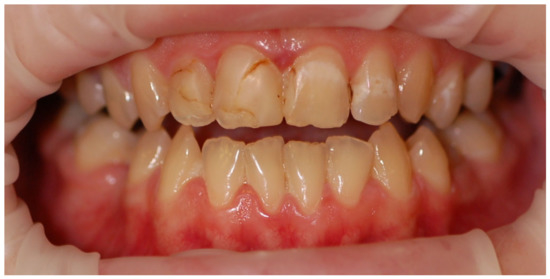

Examples of erosive defects occurring in the examined patients are presented in Figure 6, Figure 7a,b and Figure 8a–c.

Figure 6. Woman, 26 y.o. Perimylolysis in a patient with the main diagnosis: mixed neurotic disorder, showing symptoms of eating disorders.

Ijerph 20 04792 g006